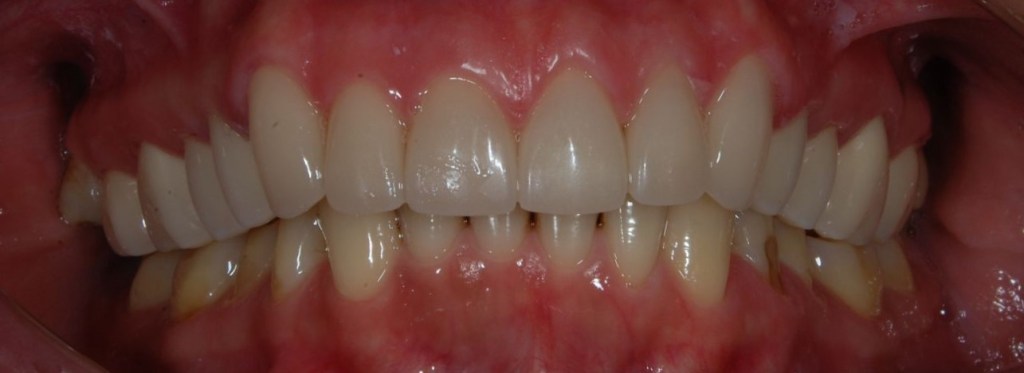

Esztétikai kezelés: felső front műanyag híd cseréje, fogak karakterizálása.

A választott korona típusa: CAD/CAM (komputer vezérelt tervezés/megmunkálás) technológiával készült cirkónium (fémmentes) szóló koronák, illetve híd.

A választott fogszín: D2

A protetikai munka elkészülésének ideje: 5 munkanap.